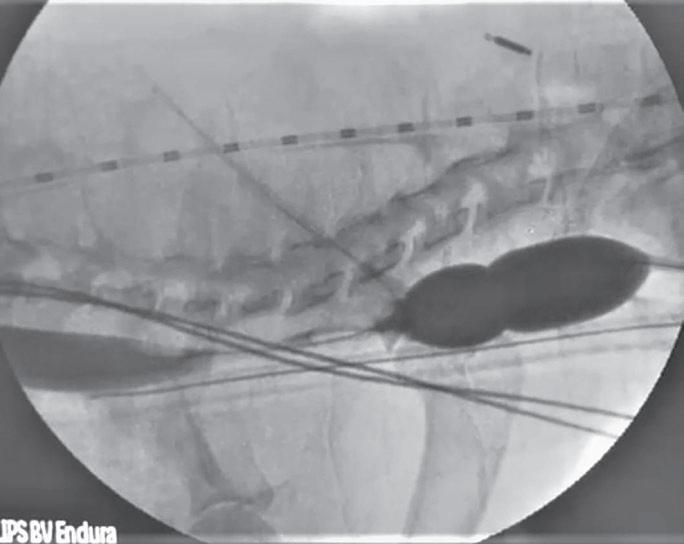

La radiología intervencionista es una especialidad que se encarga del diagnóstico y tratamiento de una gran cantidad de patologías de una forma mínimamente invasiva. Para realizar estos procedimientos es imprescindible disponer del equipamiento adecuado, tener nociones tanto de la instrumentalización como de las diferentes técnicas, y conocer con precisión la anatomía del paciente. Se trata de técnicas cada vez más implementadas en la clínica diaria ya que permiten solucionar diferentes patologías con una menor agresión a nivel tisular, una rápida recuperación, son procedimientos sin dolor, rápidos y seguros, suponen un menor coste respecto a otras cirugías invasivas, y constituyen una alternativa terapéutica a pacientes que no se pueden operar de forma convencional. Entre las más frecuentes destaca el cierre del conducto arterioso persistente, valvuloplastias en estenosis pulmonar, oclusión de shunts portosistémicos, implantación de marcapasos y colocación de stents

Para realizar la mayoría de los procedimientos quirúrgicos, es imprescindible disponer de un equipo de fluoroscopia, que permite la adquisición rápida de

imágenes basadas en rayos X y posteriormente las convierte en una señal de vídeo en tiempo real. Estas imágenes pueden manipularse ofreciendo funciones como la angiografía de sustracción digital, mapeo vascular y ampliación. Respecto a una radiografía, la exposición de rayos X necesaria para realizar una fluoroscopia es baja, pero debido a la duración de las series de imágenes que habitualmente se toman, el nivel de exposición en los pacientes suele ser elevado. Por lo tanto, es importante controlar el tiempo de exposición y llevar un registro de este. El fluoroscopio debe estar situado en una sala adecuada para su uso seguro, y todo el personal que entre en la sala de fluoroscopia debe protegerse de la radiación utilizando un delantal plomado, protectores de tiroides y gafas plomadas.